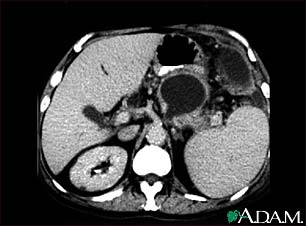

Pancreatic pseudocyst, CT scan

A CT scan of the upper abdomen showing a pseudocyst in the corpus, or tail, of the pancreas.